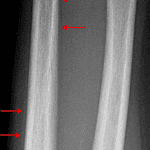

Age: 9

Sex: Female

Indication: Fall

Findings

- Broad-based apex dorsal curvature of the radial and ulnar diaphyses without fracture line

Diagnosis

- Bowing (plastic) fractures

Broad-based apex dorsal curvature of the radial and ulnar diaphyses without fracture line, concerning for radial and ulnar bowing fractures.

No fracture line identified.

Alignment appears maintained at the elbow and wrist on this limited assessment. Consider dedicated elbow and wrist radiographs for further evaluation.